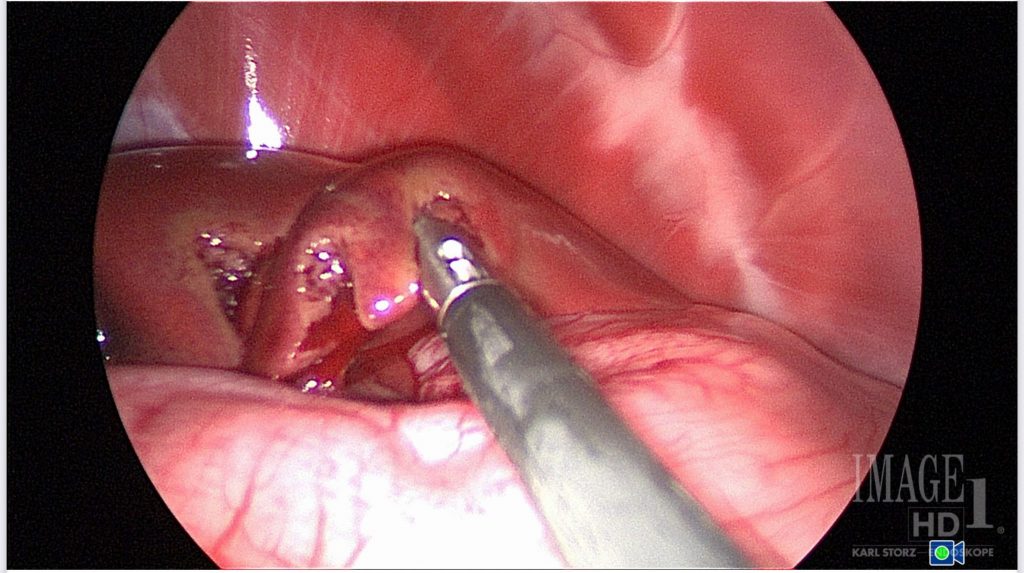

Advanced imaging and the use of fluorescence have enabled the expansion of minimally invasive surgery to procedures previously performed as open surgeries. Recent literature has shown the feasibility of laparoscopic caudal abdominal lymph extirpation using indocyanine green fluorescence, which improves visualization and dissection of the nodes.13-14 In older and more debilitated patients where two approaches may be necessary, such as with paired anal sacculectomy and caudal abdominal lymph node extirpation, laparoscopy can eliminate the need for a larger incision size and provide a quicker surgical time compared to open (Figure 2).

Figure 2. Medial iliac lymph node extirpation in a dog with high-grade mast cell tumor. Photo courtesy Dr. Maureen Griffin-Waltz